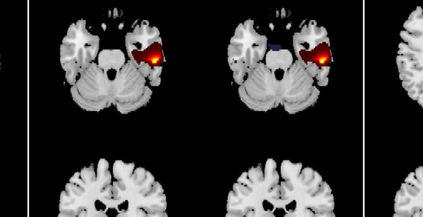

In the last two decades, unsupervised latent variable models---blind source separation (BSS) especially---have enjoyed a strong reputation for the interpretable features they produce. Seldom do these models combine the rich diversity of information available in multiple datasets. Multidatasets, on the other hand, yield joint solutions otherwise unavailable in isolation, with a potential for pivotal insights into complex systems. To take advantage of the complex multidimensional subspace structures that capture underlying modes of shared and unique variability across and within datasets, we present a direct, principled approach to multidataset combination. We design a new method called multidataset independent subspace analysis (MISA) that leverages joint information from multiple heterogeneous datasets in a flexible and synergistic fashion. Methodological innovations exploiting the Kotz distribution for subspace modeling in conjunction with a novel combinatorial optimization for evasion of local minima enable MISA to produce a robust generalization of independent component analysis (ICA), independent vector analysis (IVA), and independent subspace analysis (ISA) in a single unified model. We highlight the utility of MISA for multimodal information fusion, including sample-poor regimes and low signal-to-noise ratio scenarios, promoting novel applications in both unimodal and multimodal brain imaging data.